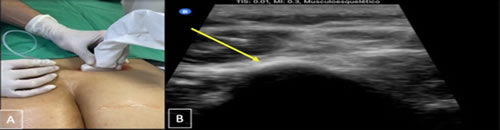

Figura 1

Figura 2

Figura 3